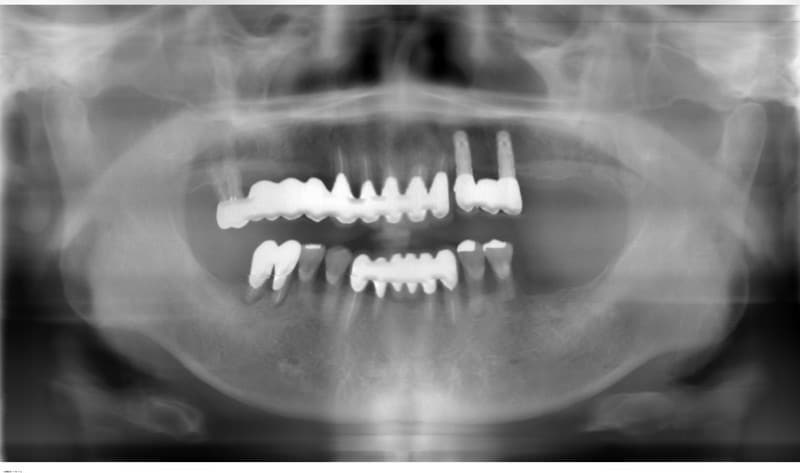

完全に歯がない場合

従来の治療

土台になる歯がないため総入れ歯となります。

うまく合わない場合は、食事がおいしくない、うまく話せない、外れやすいなどの問題が生じることがあります。

インプラント治療

インプラントを土台にして入れ歯を安定させ、動かず、しっかりした義歯にすることが出来ます。

また、あごの状態によってはインプラントによって一本ずつの歯を自然な状態で再建することも可能です。